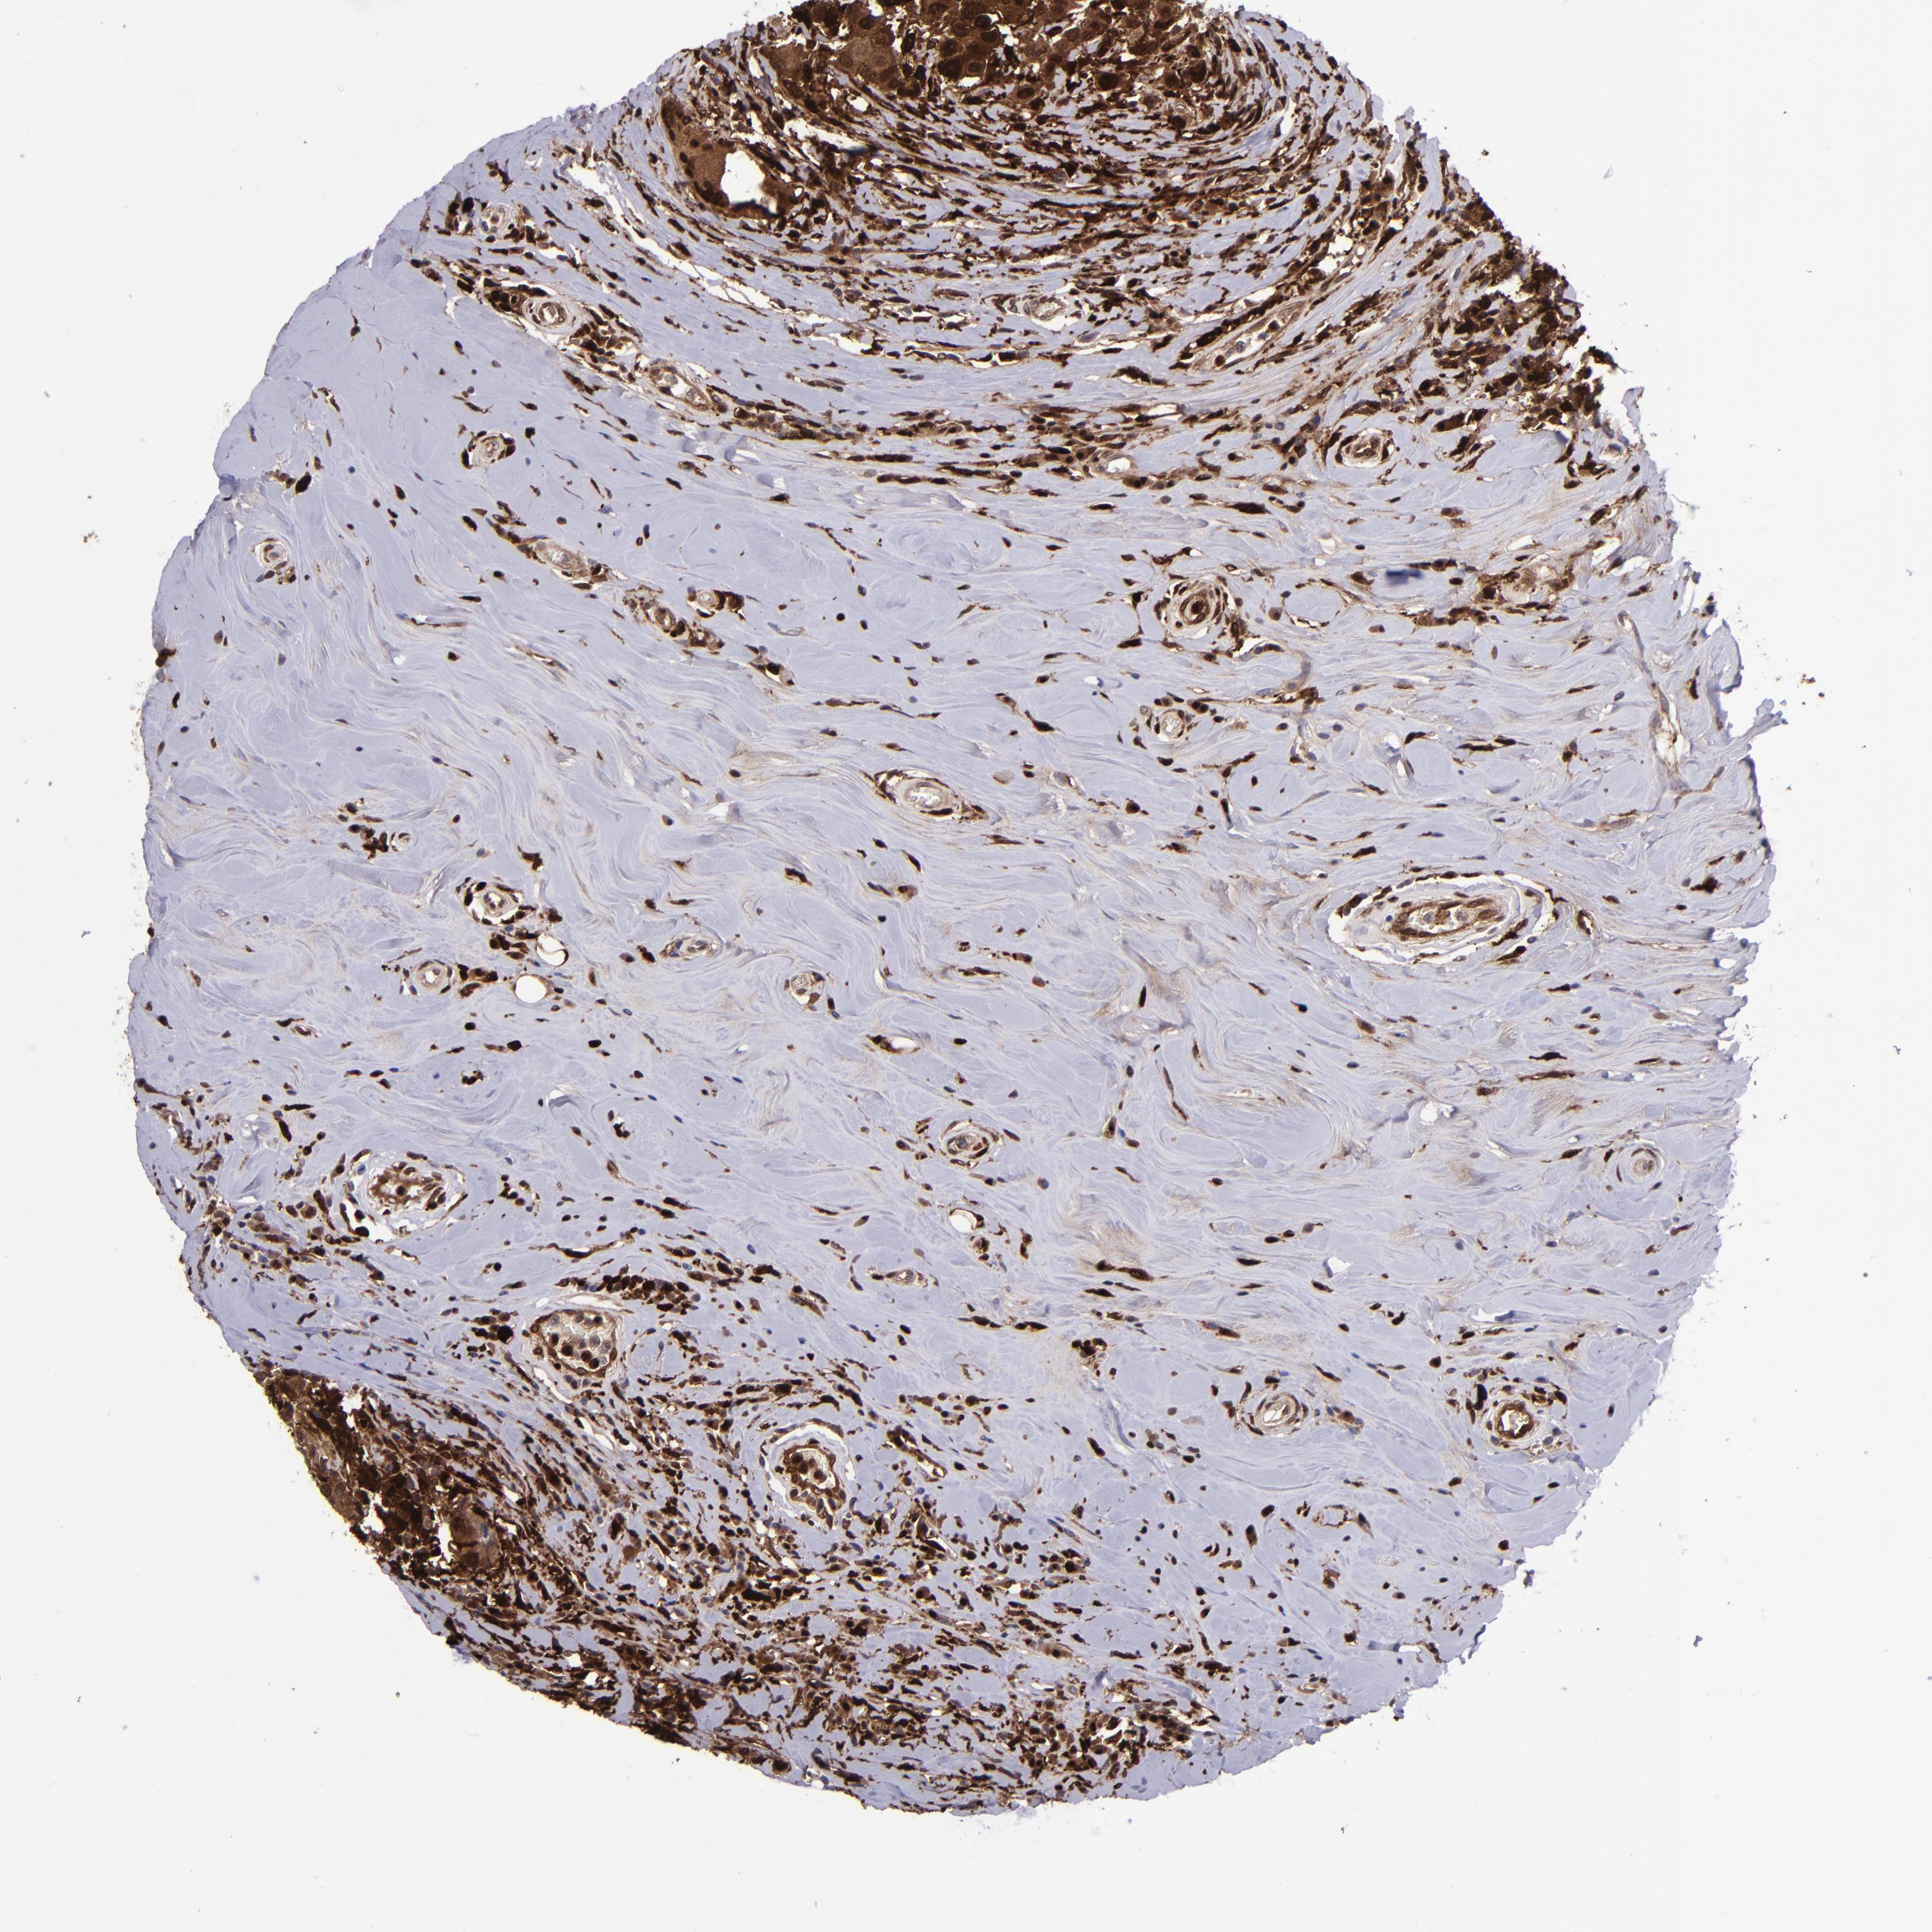

BRCA TCGA BRCA VALIDATION PROTEIN EXPRESSION

ANTIBODIES

AND

VALIDATION